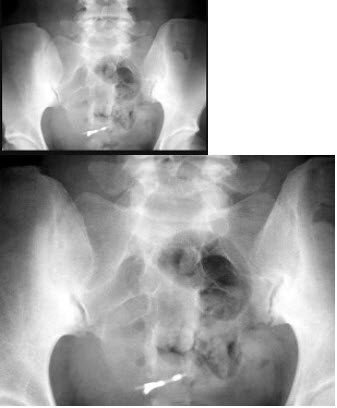

女,45岁,骶髂部疼痛3月余,结合图像,最可能的诊断是()

A.骶髂关节骨折

B.骶髂关节结核

C.骶髂关节炎

D.骶髂骨骨囊肿

E.骶髂骨骨脓肿

点击查看答案